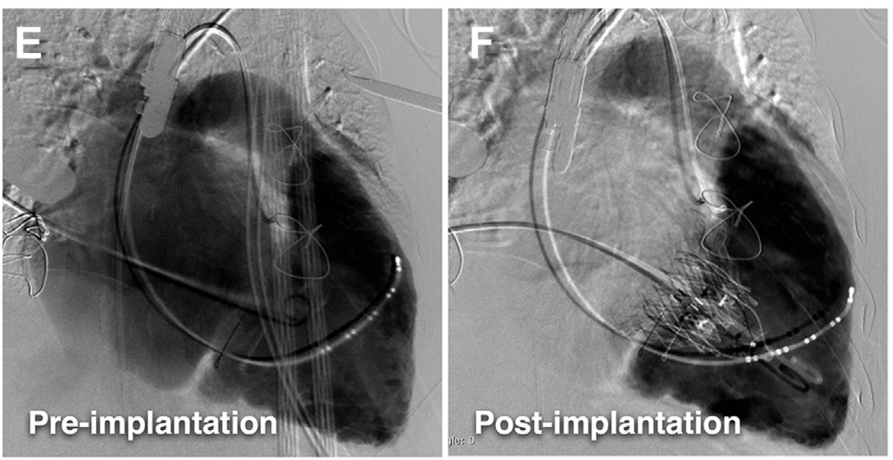

新指南推荐对于有症状的重度继发性TR患者,经心脏瓣膜中心评估无法进行外科手术,可考虑进行经导管治疗(IIb),并引用了健世科技三尖瓣置换系统LuX-Valve首次人体试验(FIM)的研究结果。值得一提的是,这是指南首次将经导管三尖瓣介入治疗纳入推荐,更是中国三尖瓣介入产品数据首次被国际指南采纳,是一次历史性的突破!该FIM研究属于早期可行性临床试验,纳入12例重度TR患者,结果显示患者的三尖瓣返流和NYHA心功能分级显著改善3(图1)。随后于2020年9月,LuX-Valve的多中心可行性临床试验正式完成,纳入31例受试者,出院及30天的全因死亡率为0,介入手术成功率为96.77%,且大部分受试者的心功能在术后得到大幅度提升(图2)。从早期的可行性试验到后期规模更大的可行性试验,LuX-Valve也经历了从技术路径到安全性、有效性的进一步验证。据了解,目前健世科技LuX-Valve确证性临床试验也已全部完成入组。全球范围内尚无同类产品完成此类试验,LuX-Valve有望成为全球首款商业化的经导管三尖瓣介入置换产品!

术前和植入LuX-Valve术后造影效果

图1.对比基线和植入LuX-Valve后TR和NYHA改善效果 (早期可行性研究)